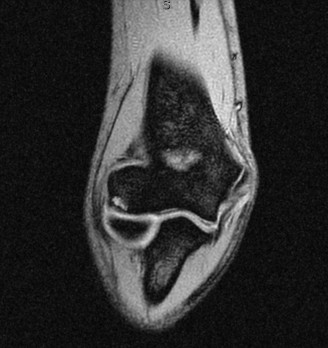

Understand common complications associated with performing surgery for scapulothoracic bursitis? CASE 33 A 42-year-old female presents to the office for follow up after sustaining a minimally displaced radial head fracture 3 months prior. She states she was initially treated in long-arm splint by the ER and did not follow up with an orthopaedic surgeon until now. Per her report, she removed the splint 4 weeks after the injury, but did not move her elbow due to pain. She now has no pain but is unable to reach that hand to her face or head. The remaining history is significant for previous ulnar nerve surgery for which she is unable to provide details. On physical examination, her upper extremity is normal except for limited flexion/extension, measured to be 80 to 50 degrees by goniometer. In addition, she has a well-healed surgical incision about the medial elbow, consistent with a previous surgery on her ulnar nerve. Her images are shown (Figs. 2–82 to 2–84).

Figure 2–82

Figure 2–83

Figure 2–84

What is the diagnosis?

- Early post-traumatic intrinsic joint contracture

- Late post-traumatic extrinsic joint contracture

- Late combined post-traumatic joint contracture

- Early combined post-traumatic joint contracture

Discussion

The correct answer is (A). Classification of post-traumatic elbow stiffness allows for better understanding of the disease and allows the clinician to treat the underlying cause of the joint contracture. Intrinsic causes include: any problem within the joint such as incongruency, loose bodies, or severe osteoarthritis. Extrinsic causes include capsular tightness, muscle contracture, heterotopic ossification, and skin contractures. Early is defined as within 6 months of the injury while late is considered to be greater than 6 months after the injury. Patients that present in the early time frame have a significantly better chance at having a good result both from nonoperative and operative treatment.